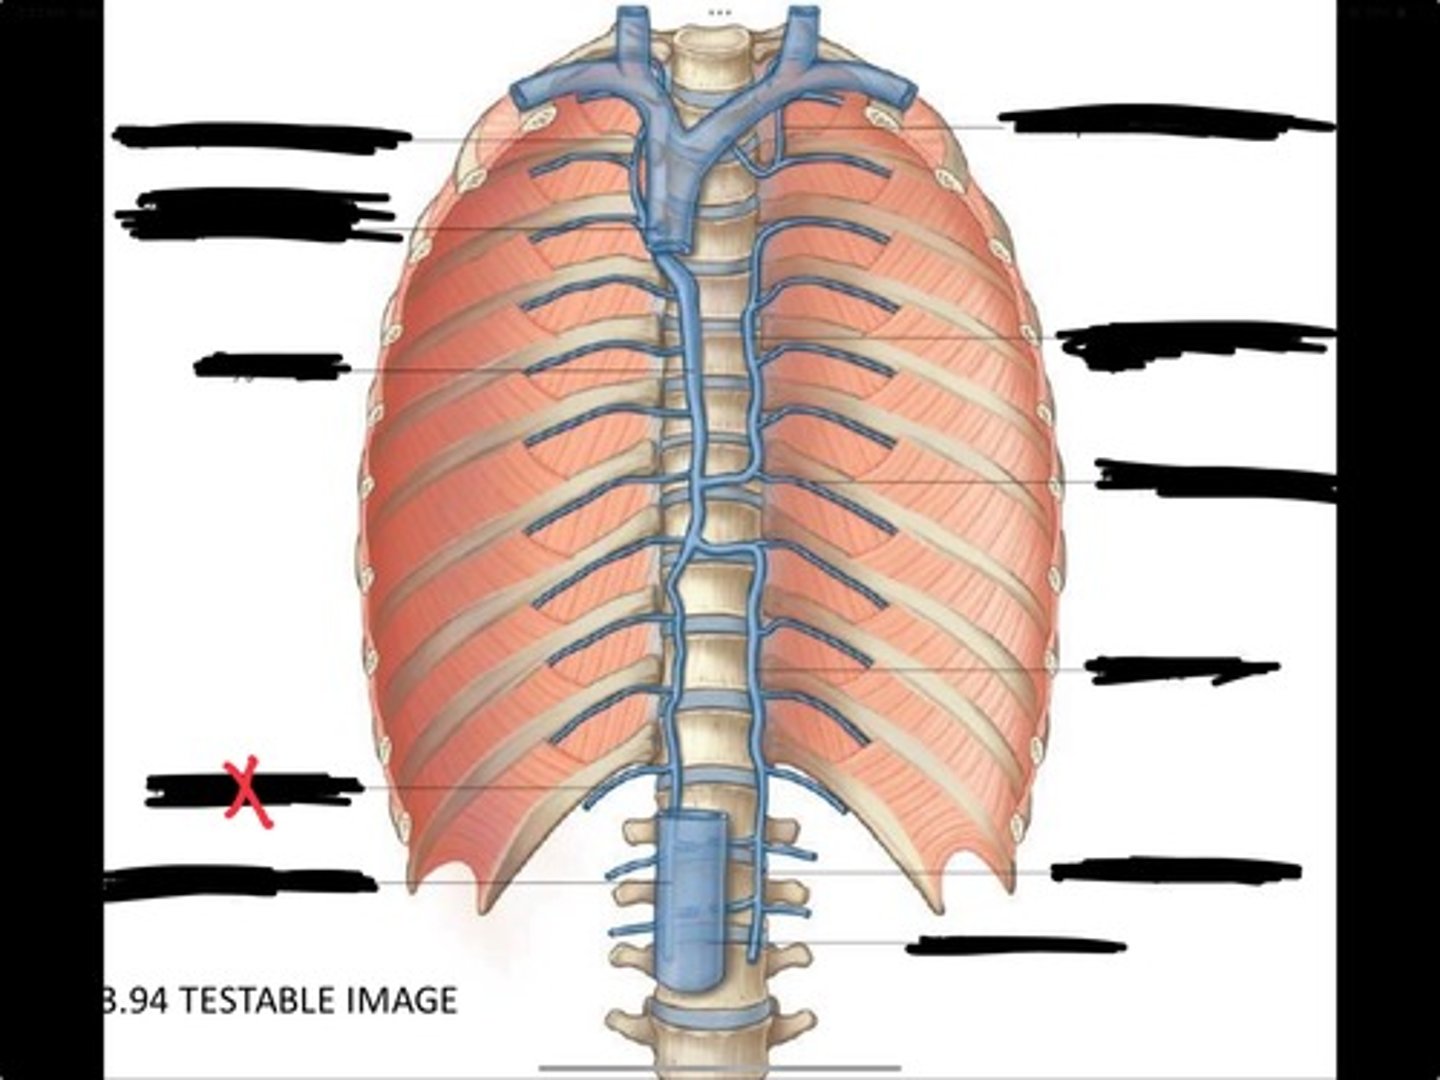

Right ascending lumbar vein

Right subcostal vein

Azygos vein

Opening of the azygos vein into superior vena cava

Right superior intercostal vein

Left superior intercostal vein

Accessory hemiazygos vein

Posterior intercostal vein

Hemiazygous vein

Ascending lumbar vein